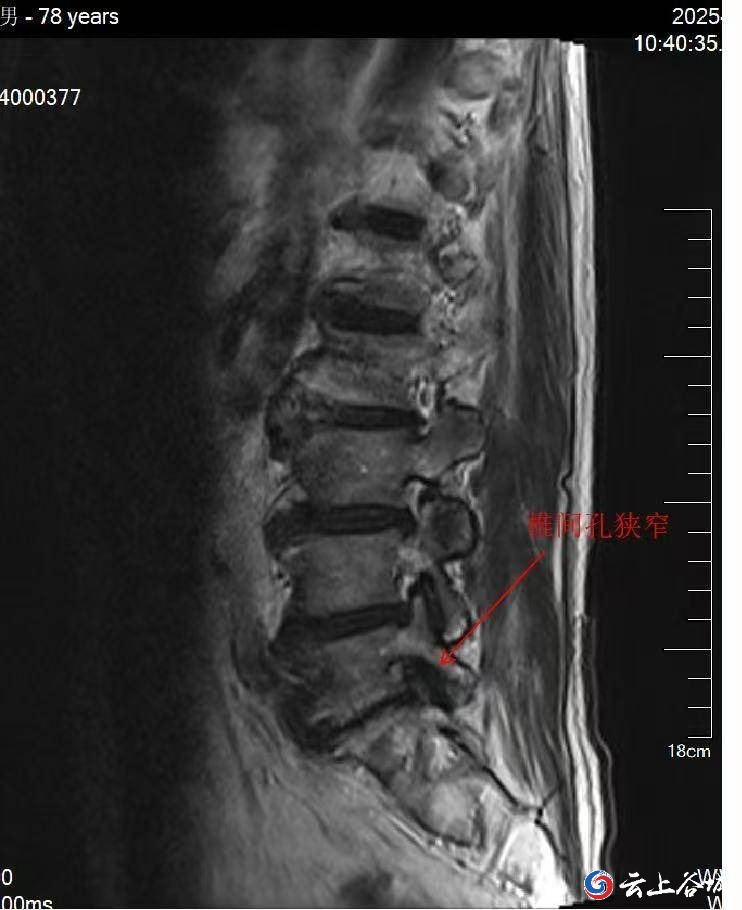

MRI提示:检查发现侧隐窝狭窄、小关节增生等。